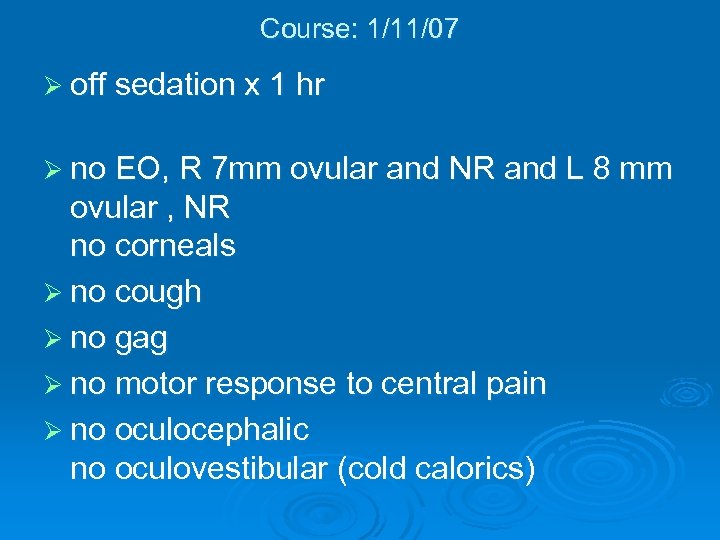

Course: 1/11/07 Ø off sedation x 1 hr Ø no EO, R 7 mm ovular and NR and L 8 mm ovular , NR no corneals Ø no cough Ø no gag Ø no motor response to central pain Ø no oculocephalic no oculovestibular (cold calorics)